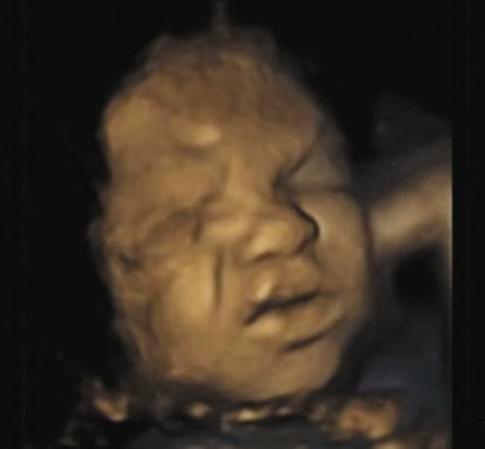

小丽怀孕6个月了,前几天去医院做排畸检查,B超照射出宝宝的样子,让小丽又好笑又无奈。

只见小家伙伸出小手,在脸上比了一个胜利的“V”字,表情更是像在做鬼脸跟妈妈互动一样,非常调皮。

看到这样的图像,小丽不禁感到担忧:“这孩子不会有什么面部畸形吧?”医生笑了笑,说:“大概率不会,就是太调皮了,哈哈。”

小丽看着娃呲牙咧嘴的模样,又好气又好笑,毕竟是自己的娃,再难看也是越看越喜欢的,儿不嫌母丑,当妈的自然也不会嫌弃娃丑啦。

这不,B超碰巧拍到小家伙的迷之举动,就把小丽给吓得不轻,还以为是娃长破相了呢,其实人家在做鬼脸自娱自乐。